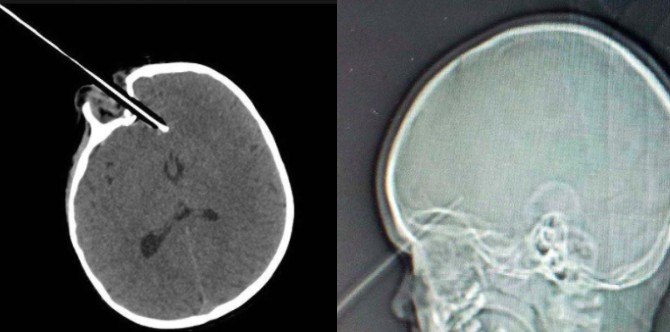

This is when she tripped on a stair gate while holding a pencil. As confirmed by an X-ray (photos above), the sharpened pencil stabbed her in the eye and then penetrated all the way into 1 1/2 inches of the front of her brain.

Toddler’s eye stabbed by pencil in freak accident: The pencil pierced through the toddler’s eye and lodged itself into her brain, just missing vital arteries. | Images from: Medicare Video